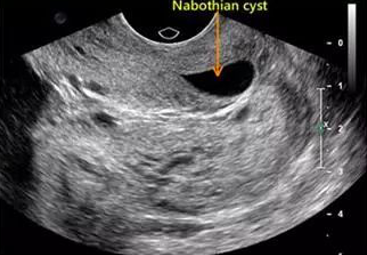

卵巢液性暗区

图片

图源:参考文献

首先,超声检查发现卵巢液性暗区≠卵巢囊肿。

因为卵巢是周期性变化的,但是也会出现一些特殊情况,如:发育大的卵泡没有排出继而黄素化,而是慢慢被体内吸收掉,从而在超声检查中表现为「卵巢液性暗区」,这种情况本身不是卵巢肿瘤,是属于月经周期中的常见生理现象,并不是真正意义上的病理变化。

因此,如果超声检查发现「卵巢液性暗区」,需要鉴别卵巢肿物属于实性还是囊性的。

如果卵巢肿物小于 5 厘米而且属于囊性,建议下一次月经干净后再进行一次超声检查,以排除卵巢生理性囊肿。

但是,如果随诊 3 个月或口服避孕药 2~3 个月,囊肿持续存在或增大,则应考虑为病理性囊肿,如卵巢肿瘤等。